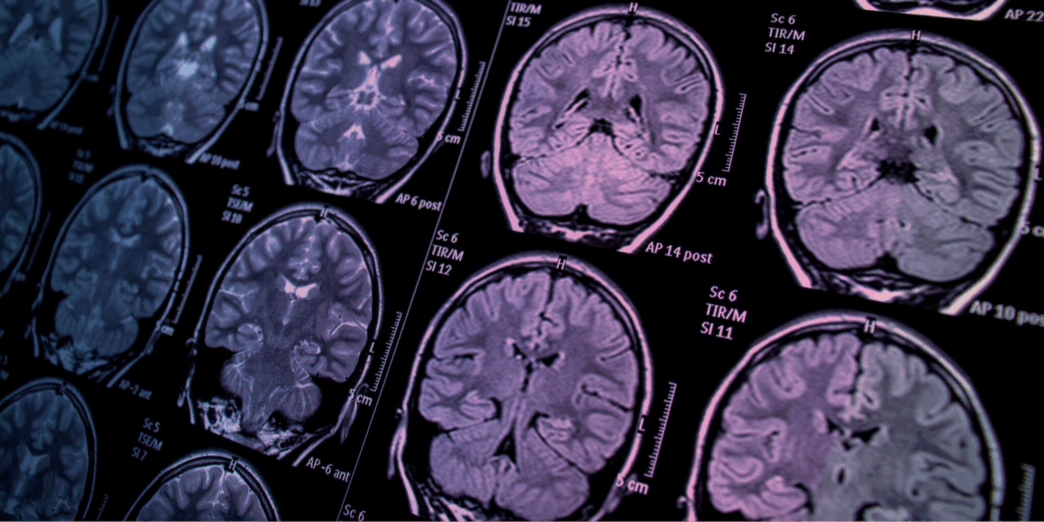

Эрдэмтэд 1.6 сая тархины зургийг ашиглан зөнөх эрсдэлийг тооцох технологи бүтээнэ

Эрдэмтэд хиймэл оюун ухааны тусламжтай 1.6 сая гаруй тархины зурагт дүн шинжилгээ хийж зөнөх өвчин тусах эрсдэлийг тооцох технологи бүтээх болжээ.

Эдинбургийн их сургууль болон Дүндийн их сургуулийн судлаачид “NEURii” нэртэй олон улсын судалгааны ажлын хүрээнд 10 гаруй жилийн турш Шотландад хийгдсэн CT болон MRI шинжилгээний зургийг судлах юм.

Тэд хиймэл оюун ухаан ашиглан шинжилгээний зургийг өвчтөнүүдийн эрүүл мэндийн түүхтэй харьцуулж, зөнөх өвчний эрсдэлийг илүү сайн тодорхойлох зүй тогтол хайна.